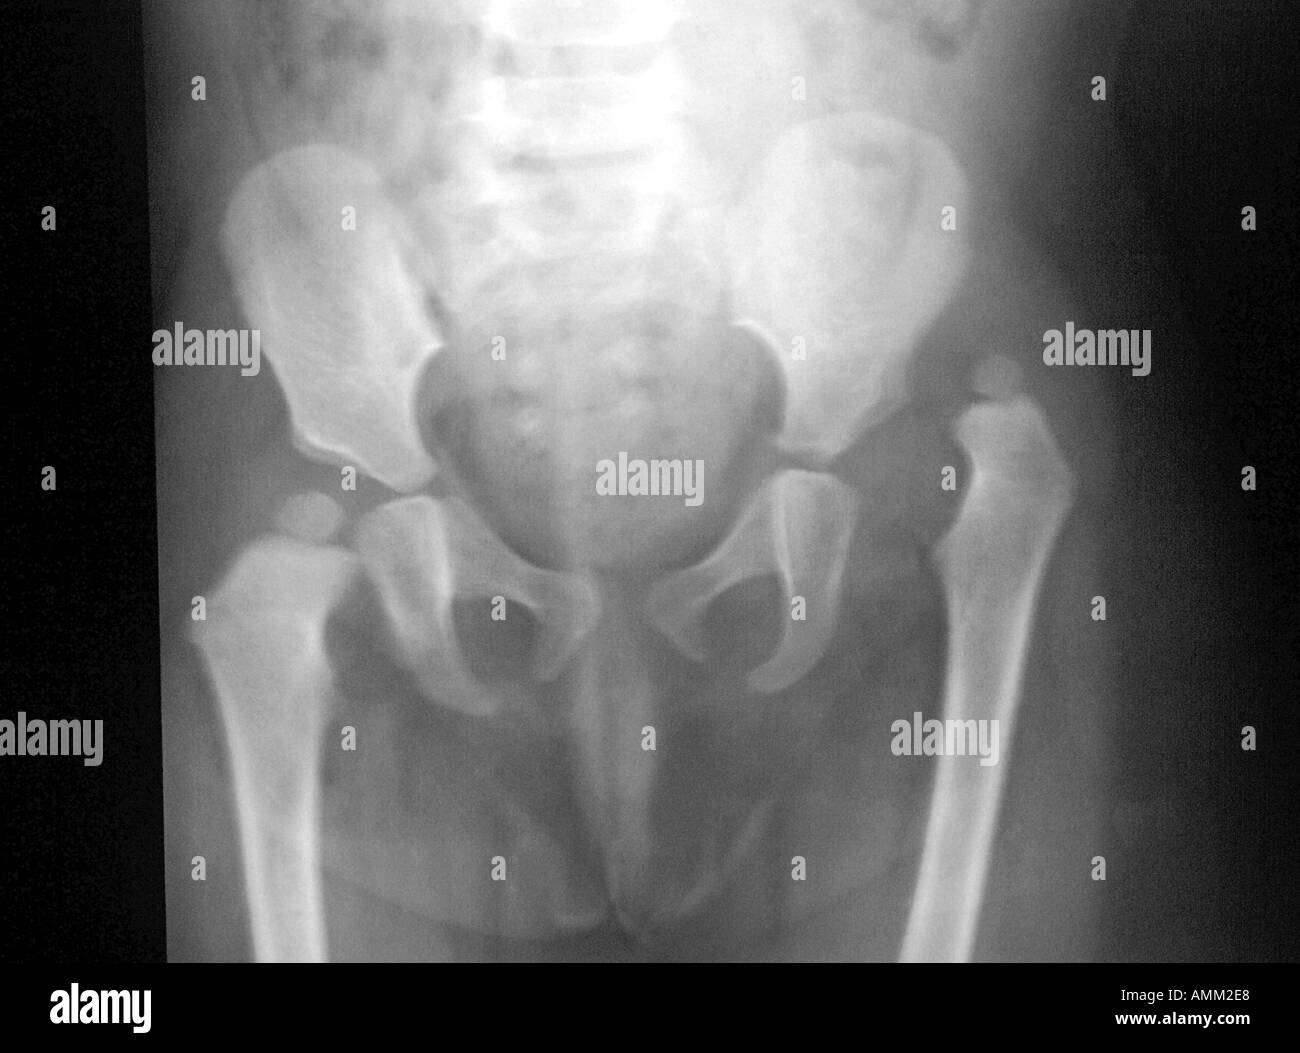

Xrays and Slides Posterior dislocation of Right hip